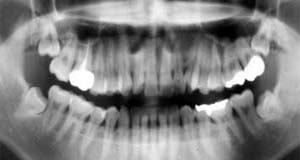

Topic No146

こんなに萠出方向が変わるものですかねぇ…

初診時 パノラマ 11年後 パノラマ

左右下顎智歯は正常萠出すると思われたが…

左右とも水平埋伏智歯に変身

初診時口腔内およびX線所見:

上顎智歯は先天欠如であったが、下顎智歯は正常方向に萠出中。

若干のカリエス治療を行ったのち、下顎智歯は萠出を待って抜歯することを約束して治療を 終了。 以後年に1度程度のスケーリングを行い経過観察をするものの、智歯抜歯の機会がないままに 11年経過。出産・子育ての一段落したことと、左側智歯の違和感を感じるようになったという ことで抜歯を決意した来院。

清掃状態が良好であったこともあり、11年間を無事経過したようですが、その間に何があっ たのか垂直方向に萠出していたはずの智歯が水平埋伏智歯に変身!?

一卵性双生児の姉も同じような経過ですが、姉の場合は左側だけが水平に変身して、 右側はほぼ正常方向に萠出。

他のも似たような症例を経験したこともありますが、これはお見事!